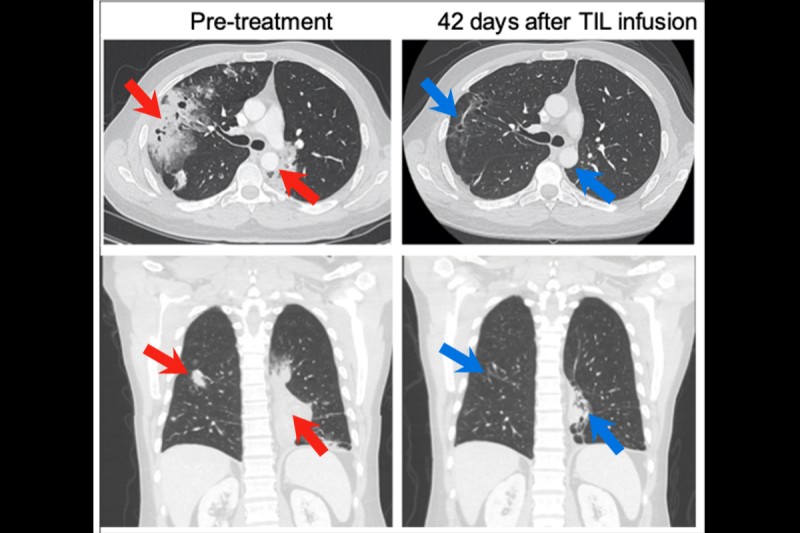

CT scans of a patient's chest illustrate how cancer has shrunk after treatment.

CT scans from a lung cancer patient treated at MSK, taken from two different views. These images show the patient’s chest before TIL therapy and again six weeks after treatment. The pretreatment images on the left reveal large areas of cancer in the chest cavity (indicated by red arrows). The post-treatment images on the right show areas where the cancer has shrunk substantially (indicated by blue arrows).

The scans of patients before and after the treatment are striking.